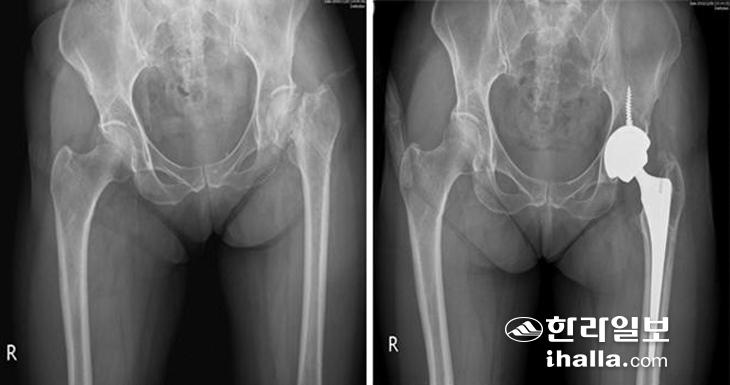

고관절 골절 중에서도 부러진 위치에 따라서 구분을 하는데 이는 골절 위치에 따라 수술 방법이 달라지기 때문이다. 대퇴골두 바로 밑의 대퇴골 경부 골절의 경우에는 골두로 가는 혈액순환이 끊어질 가능성이 높아 뼈를 붙이는 수술을 하더라도 잘 붙지 않을 수 있다. 설령 붙었다 하더라도 대퇴골두 무혈성 괴사가 발생하게 되면 지속적인 통증이 남는다. 이러한 이유로 인공관절 수술을 하는 경우가 많다. 단, 골절의 전위가 심하지 않거나 불완전 골절인 경우, 그리고 젊은 환자에서는 뼈를 붙이는 수술을 해볼 수 있다. 고관절 인공관절 치환술은 8~9cm 피부절개로 근육, 혈관, 신경 등의 조직 손상을 최소화하여 빠른 회복을 도모할 수 있으며 수술 후 안정적일 경우 3~4일이 지나면 걸을 수 있다. 그러나 수술 후 약 3개월 정도는 탈구의 위험이 있을 수 있어 쪼그려 앉기, 양반다리, 다리를 꼬는 행동을 삼가야 하며 이후에는 무리 없이 일상적인 생활이 가능하다.

▶전자간 골절 땐 내고정 수술 시행=대퇴골 경부보다 아래쪽의 대전자와 소전자를 연결하는 부분이 부러지게 되면 전자간 골절이라고 하며 인공관절로 보다는 골수정 또는 금속판을 이용한 내고정 수술을 시행하게 된다.

내고정 수술

이 부위는 대퇴골두 무혈성 괴사가 잘 발생하지 않으며, 비교적 뼈가 잘 붙는 부위다. 수술 후 3~4일 후부터 운동을 조금씩 시작하면서 고관절 주위의 근육을 강화시키는 재활을 시작한다. 과도한 운동은 고정시킨 골수정 또는 금속판이 파손될 위험이 있으므로 지양해야 하고 뼈가 약하거나 분쇄골절이 있는 경우는 6주간은 체중부하를 하지 않고 지팡이나 목발을 사용해야 한다.